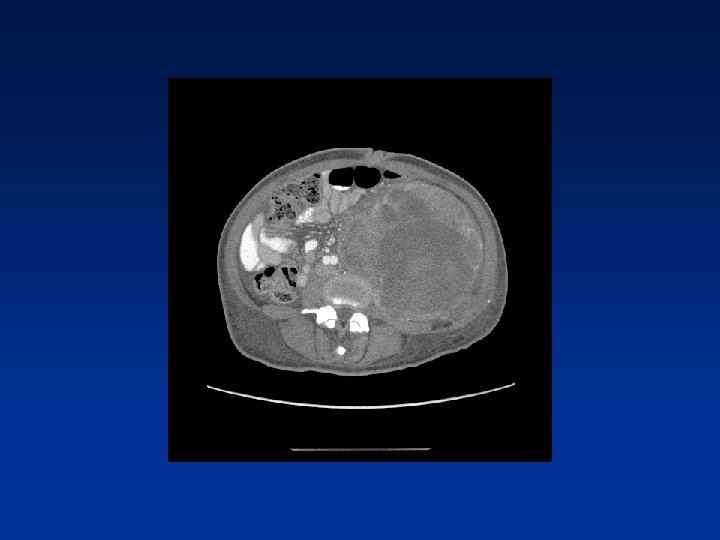

CASE